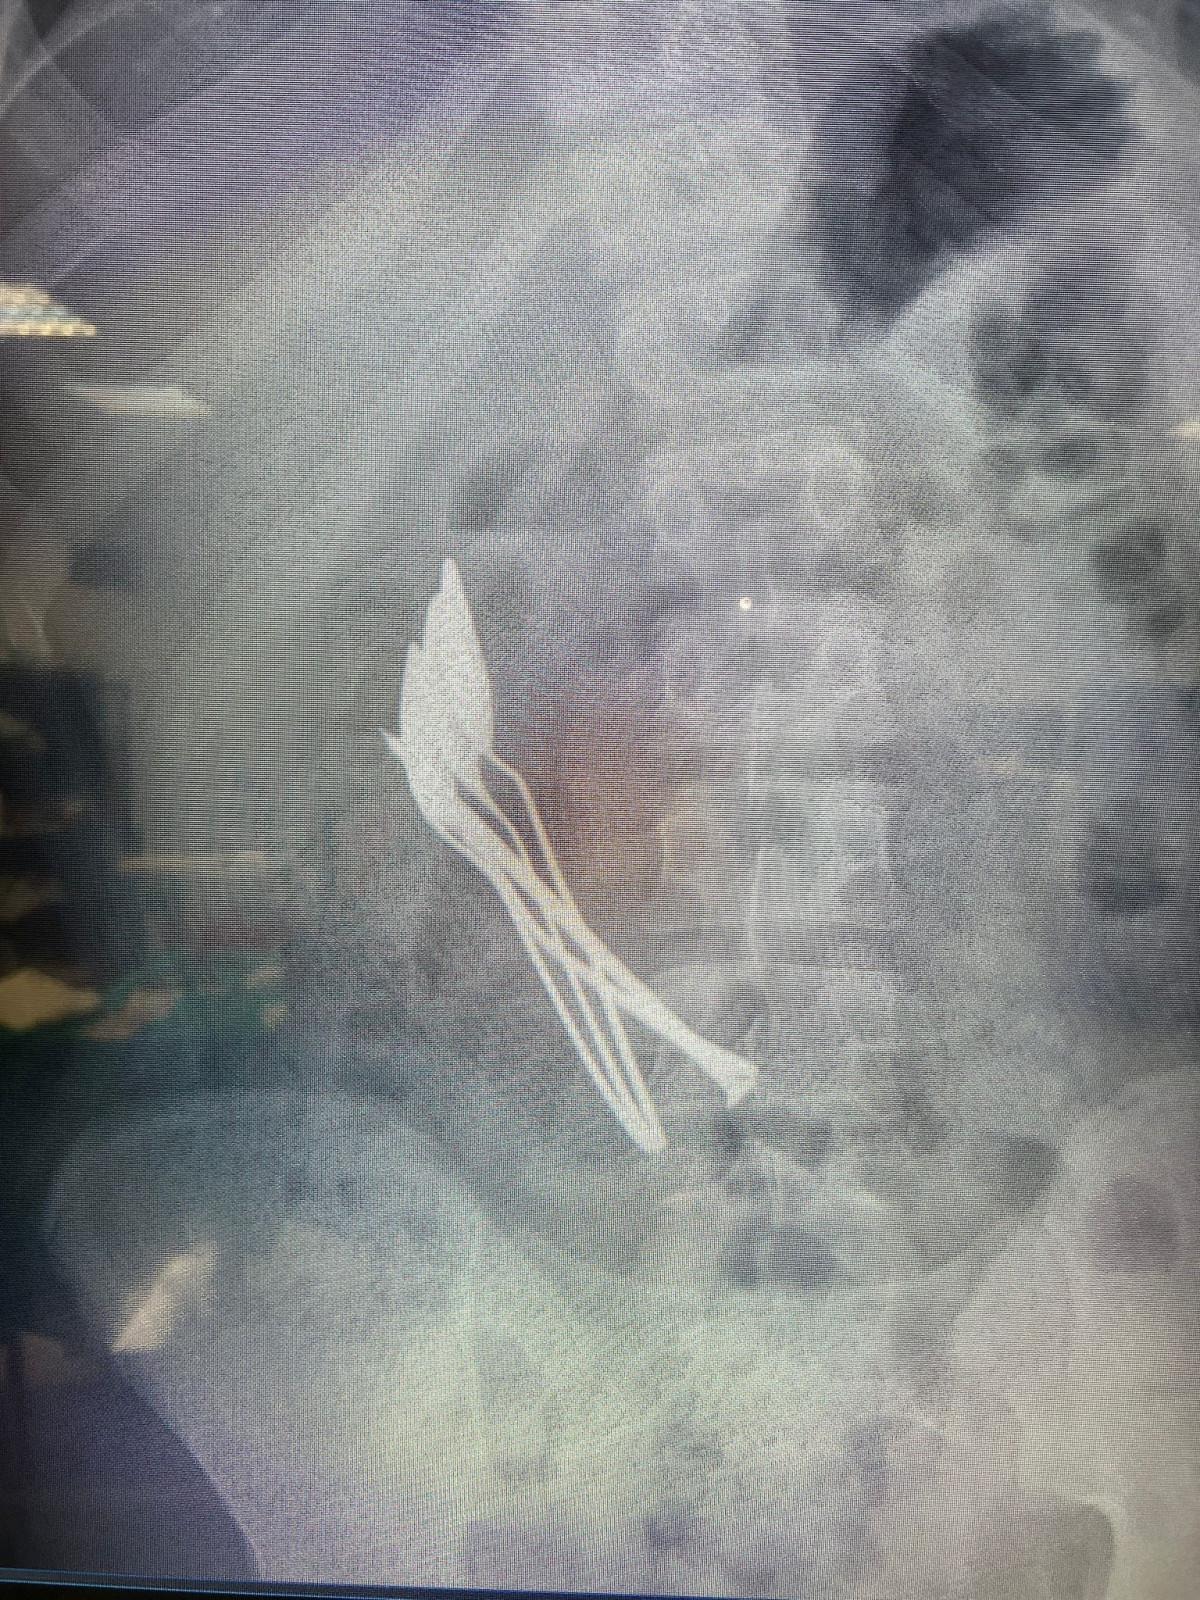

Kayseri Şehir Hastanesi’nde yapılan incelemede, çocuğun midesinde 4 metal tatlı kaşığı ve 1 çivi görüldü.

4 KAŞIK VE 1 ÇİVİ, 2 SAATLİK AMELİYATLA ÇIKARILDI

Kayseri Şehir Hastanesi Çocuk Cerrahisi ve Ürolojisi Anabilim Dalı Başkanı Doç. Dr. Mustafa Erman Dörterler ve ekibinin gerçekleştirdiği yaklaşık 2 saatlik operasyonla, çocuğun midesinden kaşıklar ve çivi başarıyla çıkarıldı.